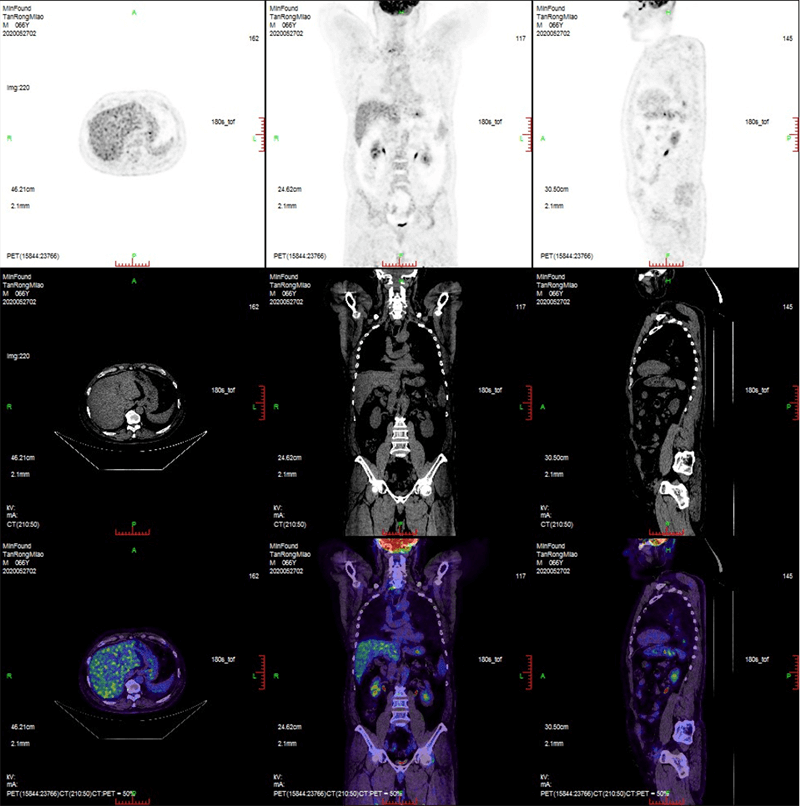

ScintCare PET/CT 720E

ScintCare PET/CT 720E uses the 4th-generation PET detector with which lutetium-yttrium oxyorthosilicate (LYSO) crystals are individually coupled to SiPM detectors without the optical conductor. This digital SiPM-based detector ensures 100% crystal coverage to the SiPM and greatly improves photons efficiency and images quality.

The 20.16 cm axial FOV compare to the conventional 16 cm axial FOV PET/CT, it speeds up the scanning process allowing greater patient throughput.

臨床畫廊